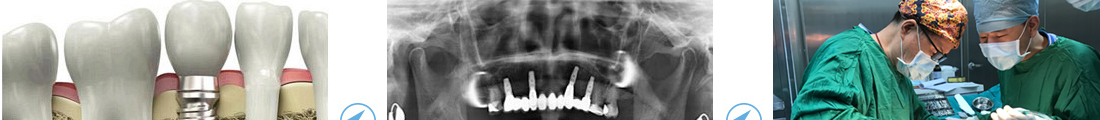

麦芽口腔数字化精确种植冲破传统种植理念,采用数字化的口腔CT及3D导板技术制定种植牙方案,并结合数字化技术,精、准、稳地植入种植体,低创微痛,即拔即种、创口微小、术后就能饮食,是目前优良的牙齿种植技术。